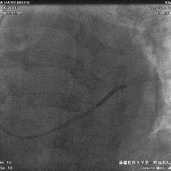

电极植入

● 植入心房电极和右室除颤电极,连接起搏器。

术中电参数

● 术中测试除颤电极感知良好,除颤阻抗正常。

➛ 心房:

1.6V/0.42ms,Pwave:2.8mv,阻抗:680欧姆

➛ 心室:

0.5V/0.42ms,Rwave:>20mv,阻抗:860欧姆

➛ 左室:

LV-tip 1.2V/0.42ms 阻抗:640欧

LV-2 1.0V/0.42ms 阻抗:600欧

LV-3 1.5V/0.42ms 阻抗:650欧

LV-4 1.4V/0.42ms 阻抗:700欧

术后心电图